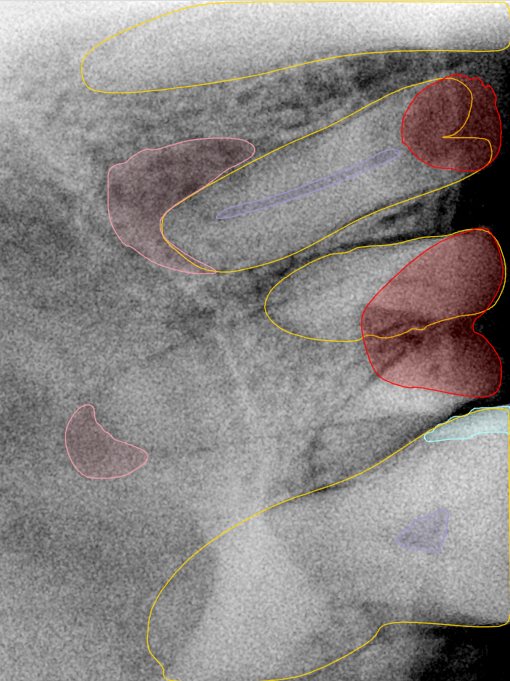

CR/DR 牙齿分割阶段记录

当前进展

- 完成了 CR/DR 牙齿相关分割训练

- 当前结果已经达到阶段预期,但仍有细节问题需要继续处理

相关测试

遇到的问题

- 训练过程中出现过 mask 下移问题

- 部分结果会出现 box 填充异常

- mask 边缘仍然有比较明显的锯齿感

第二版算法问题测试

结论:修复类出现了不鲁棒的情况,后续需要加入轮廓的扩充数据进行增强。